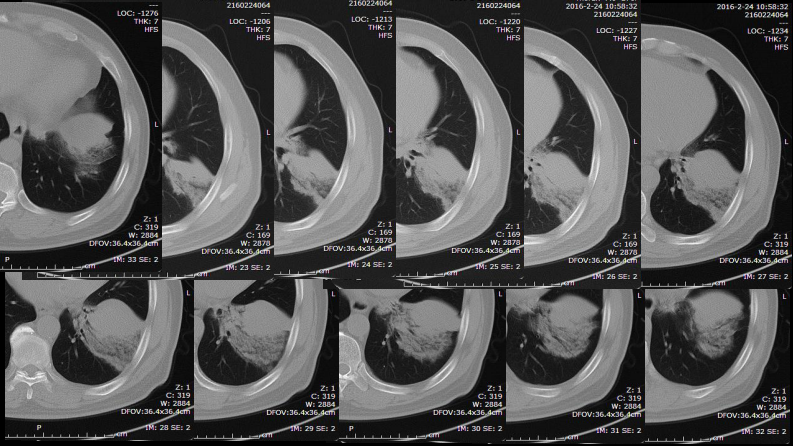

一例肺粘液腺癌综合影像及病理学回顾.pdf